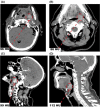

Methods: An injectable TP was developed using an agar-gelatin base, unsalted chicken stock, deionized water, food coloring for visual mimicry, and iohexol for radiographic mimicry. Four percentage glutaraldehyde was used as a cross-linking agent for solidification of the TP. The TP was then injected in various mucosal anatomic sites in four unfixed cadaver heads. Visual, radiographic, and tactile mimicry was assessed via endoscopy, CT scan, and tumor dissection and palpation, respectively.

Results: Tumor phantom injection was successfully achieved in all four cadaver heads. Visually and tactilely, the TP demonstrated similar color change, induration, and firmness of a typical squamous cell carcinoma (SCCa). However, ulceration that is often seen with SCCa could not be replicated. CT mimicry was compared with nine patients with known SCCa. Tumor radiodensity in the nine patients was between 77 and 110 HU (mean 86.3 HU) whereas TP radiodensity was 59 and 127 HU (mean 93.7 HU), with no significant difference between groups (P = .21).